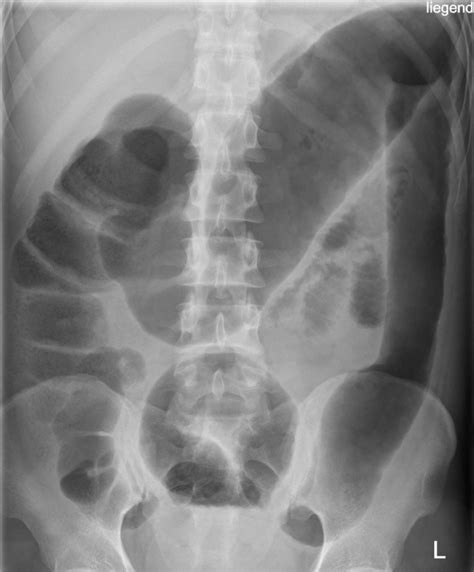

• Constipation: One of the most common symptoms is chronic constipation, where bowel movements are infrequent and difficult to pass.

• Abdominal Pain: Pain or discomfort in the abdominal area, often due to the buildup of waste in the colon.

• Bloating: A feeling of fullness or bloating in the abdomen, which can be uncomfortable and affect daily activities.

• Gas and Flatulence: Increased gas production and flatulence, which can be embarrassing and uncomfortable.